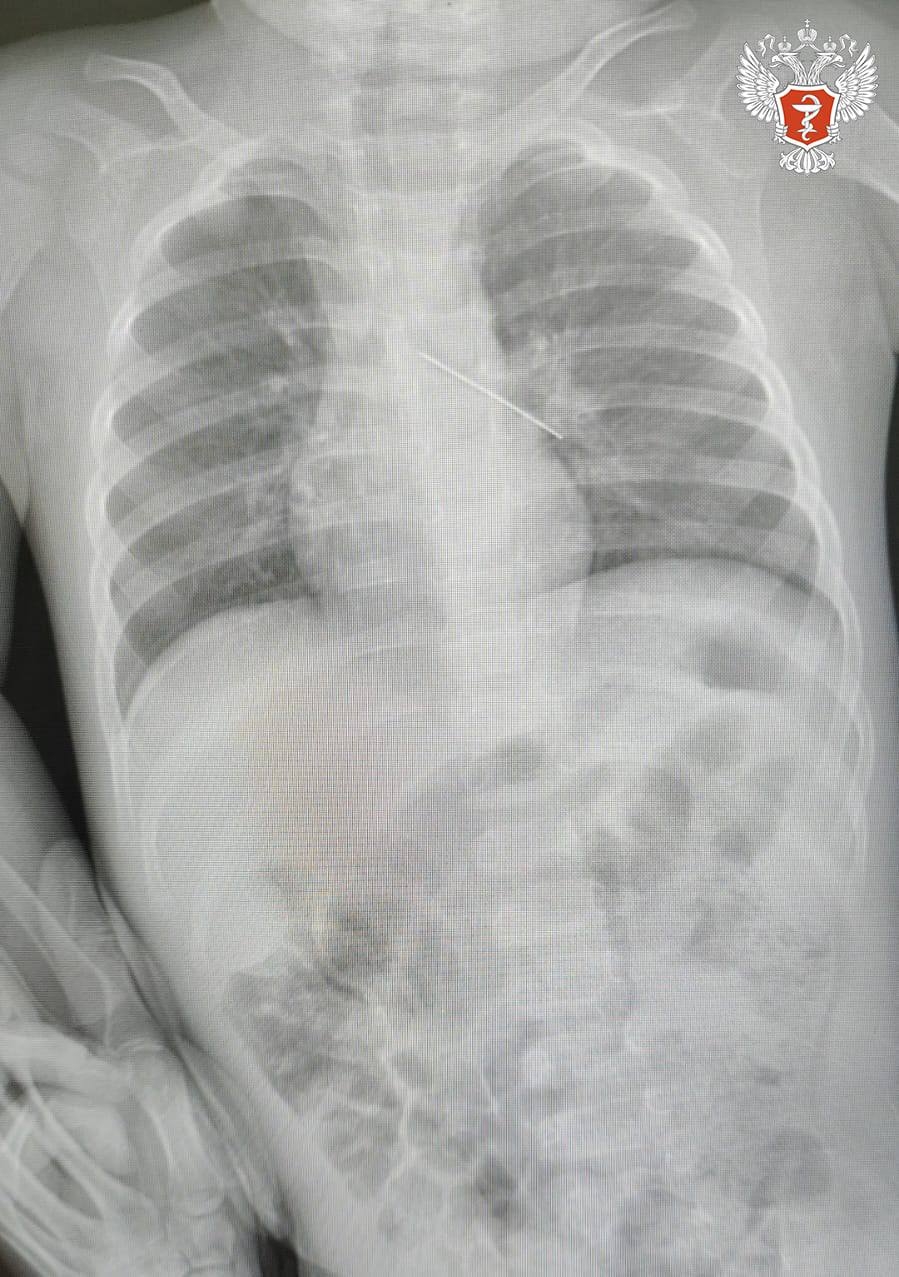

В ходе обследования врачи установили, что инородное тело оказалось в бронхах — одном из наиболее опасных мест при подобных ситуациях. Возникла угроза развития тяжёлых осложнений, включая полную закупорку дыхательных путей.

Специалисты выполнили эндоскопическое вмешательство и успешно извлекли булавку с помощью бронхоскопа.